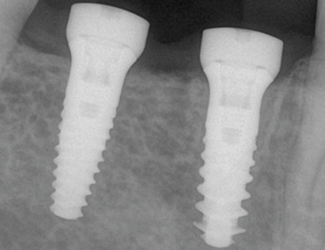

Implantatbehandling utfördes med Straumann TLX SLActive 4,5 x 10 mm RT i region 45 samt Straumann TLC SLActive 4,5 x 10 mm RT i region 46. Implantaten installerades med ett insättningsmoment på 45 Ncm. Vid initial ISQ-mätning uppvisade båda implantaten ett värde på 79, vilket indikerade god primär stabilitet. Efter åtta veckors läkning bedömdes implantaten som stabila för avtryckstagning inför permanent protetisk rehabilitering, med ett uppmätt ISQ-värde på 88.

1. Utgångsläge före implantatinstallation.

2. Implantatinstallation region 45 & 46.